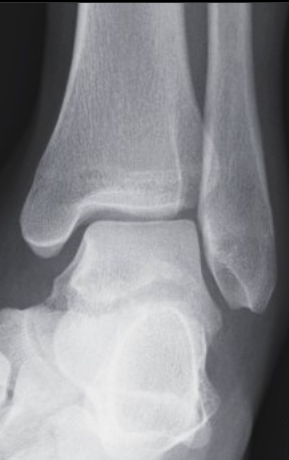

17

Q

correction

A

needs slightly more internal rotation